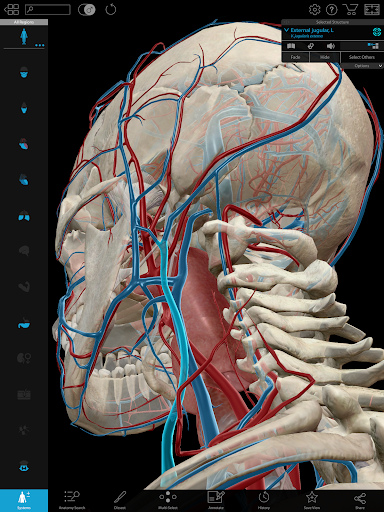

Additional nerves, arteries, and veins in the head and neck region.

Tag structures! Use the new 3D labels feature to show the name of multiple structures on screen.